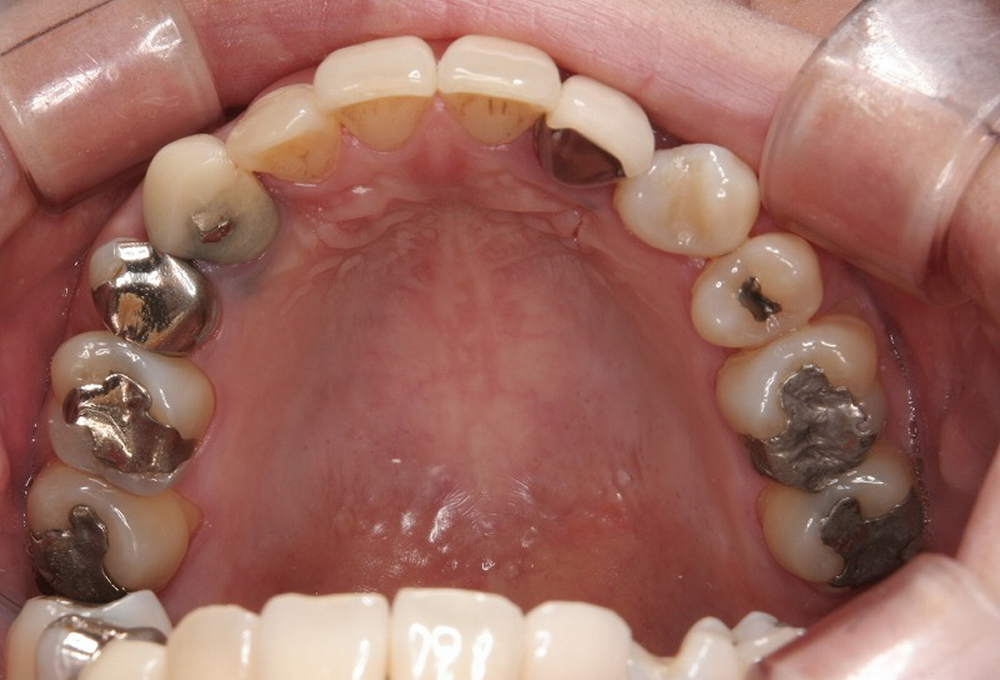

②術前 上顎